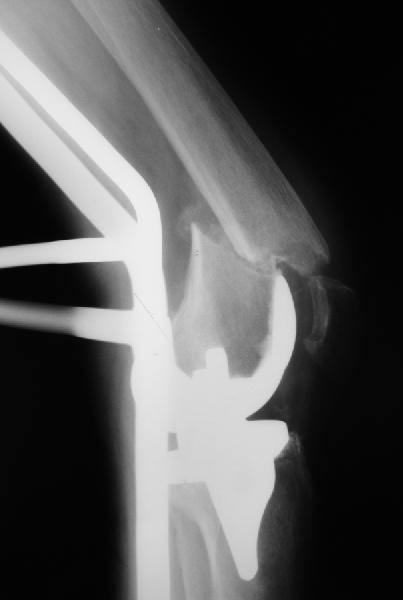

То, что планируется - наиболее распространенный подход. Еще менее инвазивный вариант - закрытый антеградный интрамедуллярный остесинтез. Мы используем гвозди, которые выпускаются предприятием ЦИТО, т.е. недорогие. Там в дистальное отверстие можно ввести 3 винта (2 снаружи и один навстречу), еще и угловая стабильность получается.